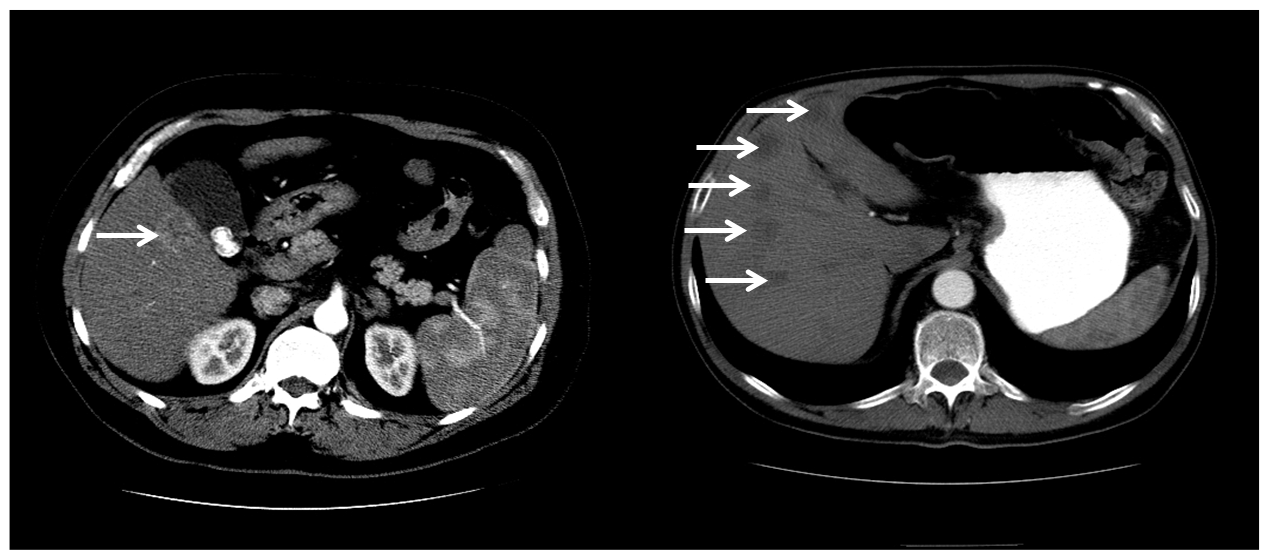

- Evidence of improved outcomes following laparoscopic liver surgery

- Retrospective studies with long-term follow-up are now being published, and early indications point to oncologic equivalence of minimally invasive approaches compared to open approaches for liver surgery.

- No randomized clinical trials have yet been published comparing minimally invasive and open approaches for liver surgery.